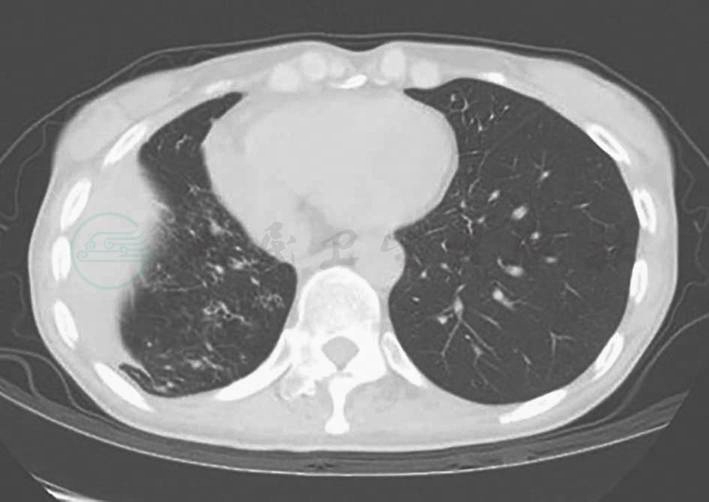

更昔洛韦抗病毒抢先治疗(具体方案为更昔洛韦静脉滴注300mg/次,q12h(每12小时1次),2周后减至300mg/d,再用2周后改为口服更昔洛韦500mg/次,3次/d,2个月),甲泼尼龙1g/d×3d冲击联合环磷酰胺400mg q2w(每2周1次),治疗后症状迅速缓解,但缓解1周后症状反复,反复查巨细胞病毒抗原均阴性,痰培养提示烟曲霉阳性,复查胸部CT提示“右中肺机化性肺炎较前吸收、右下肺支气管胸膜瘘和左肺真菌感染”,考虑为治疗过程中并发真菌感染,细菌感染不能除外,遂将甲泼尼龙减量为60mg/d静脉滴注,停用环磷酰胺,加用伊曲康唑200mg/d、哌拉西林舒巴坦5g,q12h静脉滴注,充分抗感染治疗,此后复查CT提示“机化性肺炎逐渐吸收,支气管胸膜瘘及肺部感染范围亦逐渐减小”(图4),体温正常,症状好转出院。

图4 2011年4月胸部CT示机化性肺炎明显好转